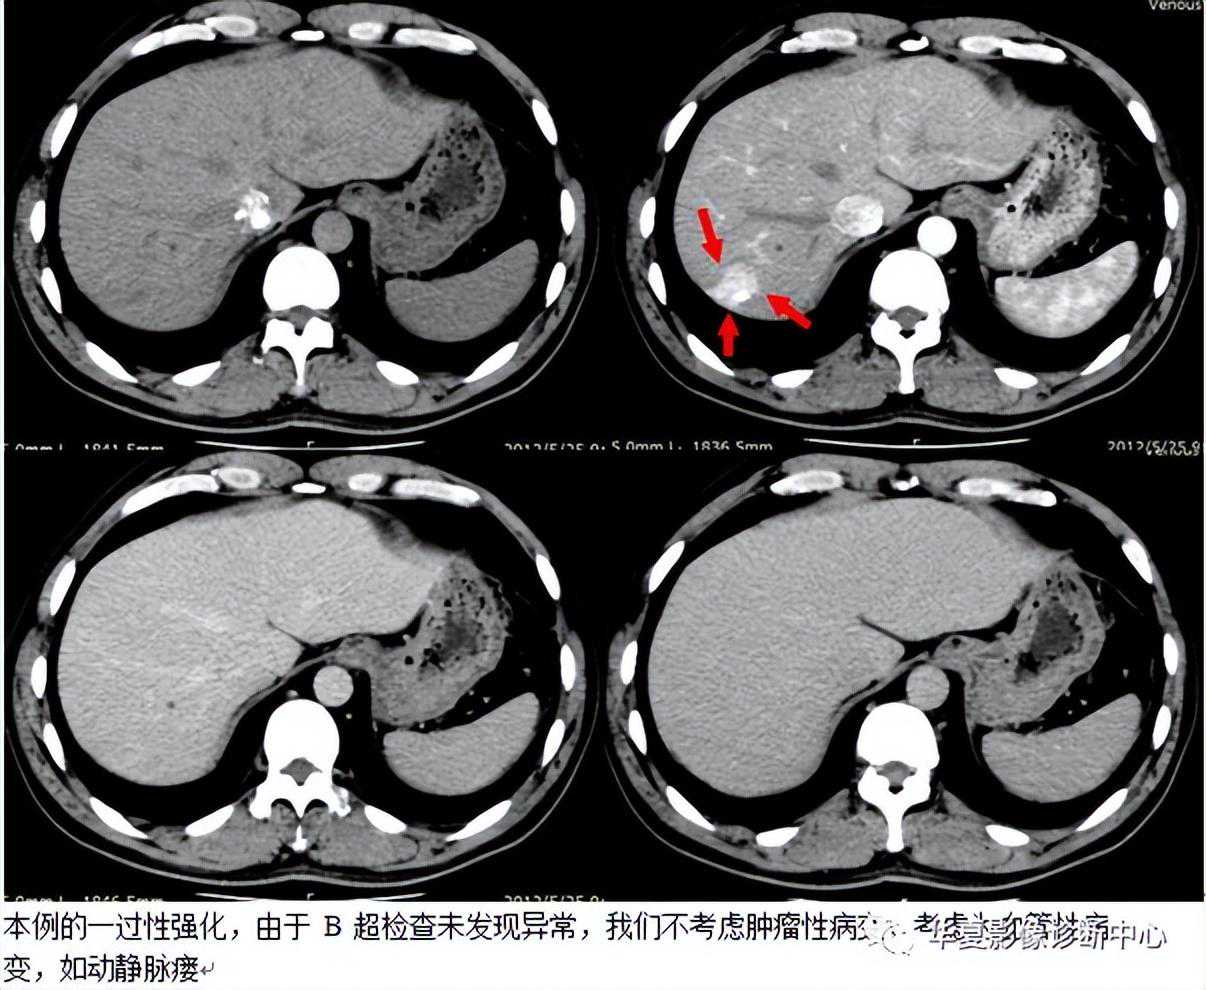

032:肝脏灌注异常(HPD)

HPD是指由各种原因引起的肝段、亚段及肝叶之间的血流灌注差异,在CT、MR动态增强扫描及肝动脉造影时表现为动脉期正常肝实质一过性楔形、三角形或类圆形强化或染色,门静脉期即恢复正常,没有占位效应、强化或染色区内可见正常血管穿行。

CT平扫大多数表现为等密度,少数表现为楔形或三角形低密度区,可能与门静脉分支堵塞后,富含营养的门静脉血流灌注减少,相应肝段出现营养不良性水肿,继发局部的脂肪变性有关。增强扫描时多表现为动脉期一过性楔形、三角形或类圆形异常强化区,少数为强化减低区,门静脉期恢复等密度。这种变化可累及肝段、亚段及肝叶,可多发,也可单发,多位于肝周围区域;MR表现类似于CT,平扫大多呈等T1、等T2信号,少数可表现为长T1、长T2,但MR在显示门静脉堵塞后继发改变较CT敏感。动态增强扫描时强化及分布特征类似于CT。肝动脉造影时见楔形、三角形肝段染色,可位于肝脏相关病灶周围或邻近肝段,有门静脉堵塞者间接门静脉造影可见相应区域染色缺失或减弱,有肝静脉堵塞及异位血管变异者会有相应造影表现;HPD时,超声可能表现为楔形低回声区,超声增强是否通过切面实时观察到HPD,尚无文献报道。但是本例超生检查未发现异常。